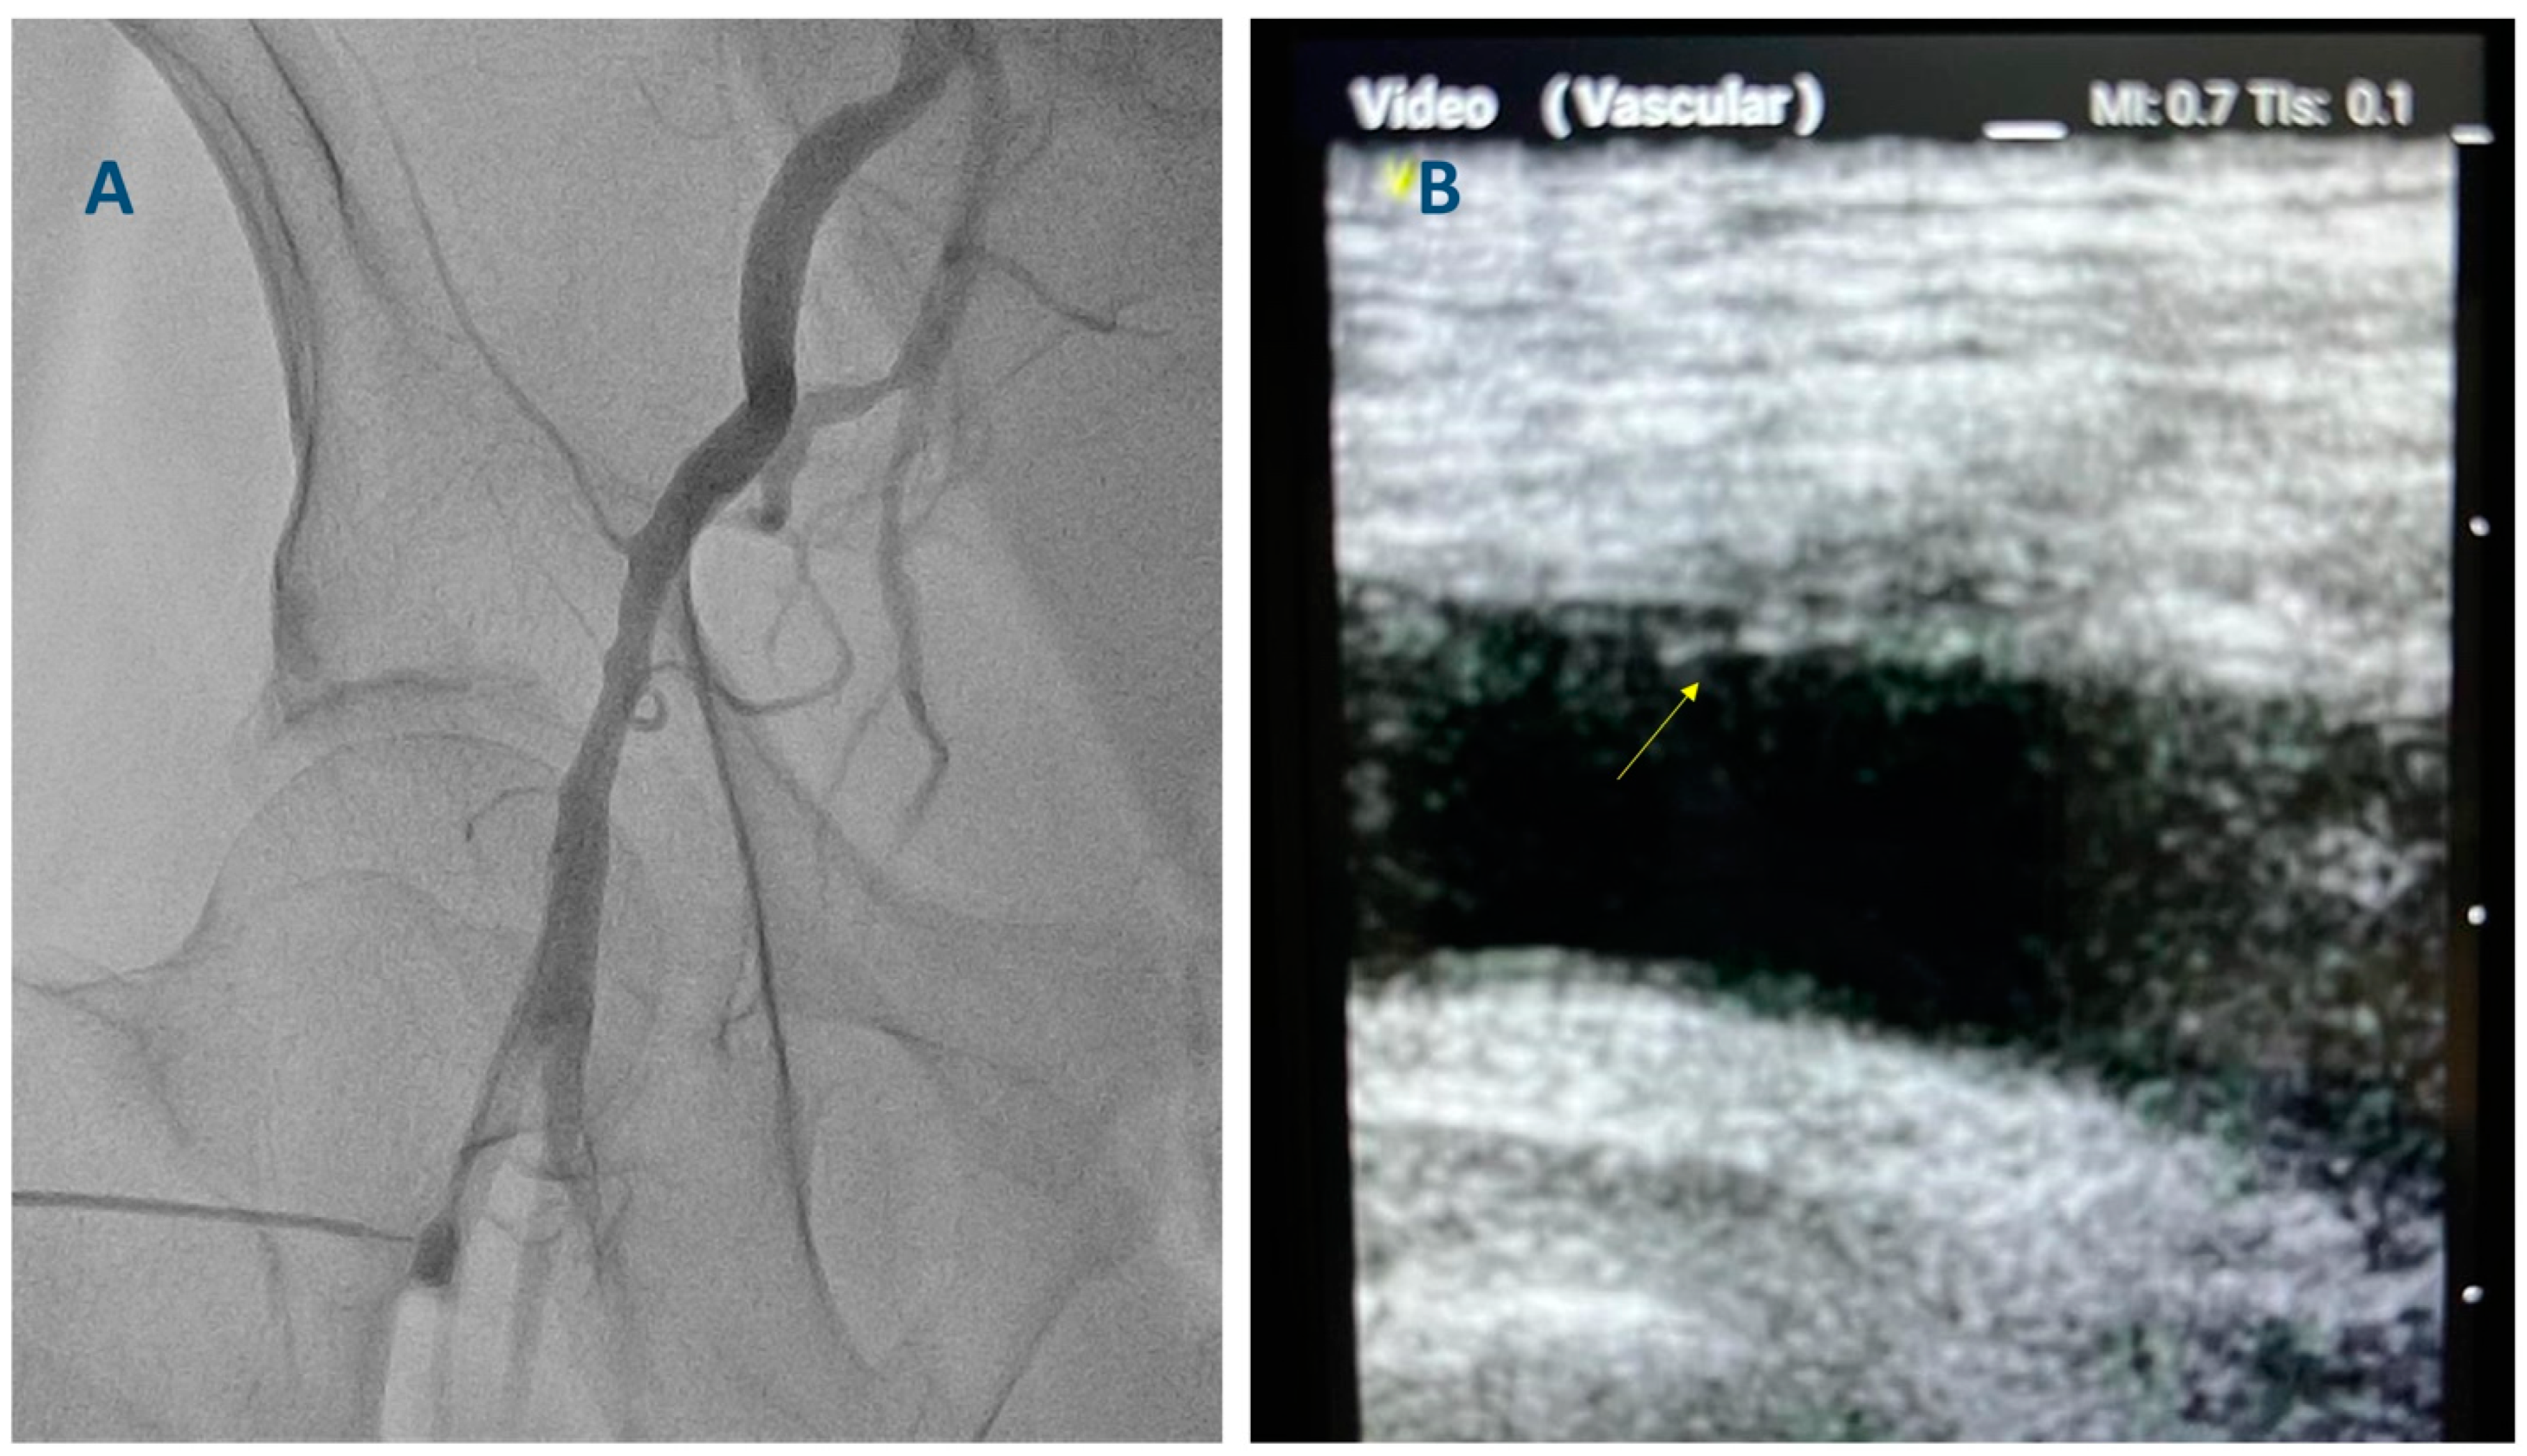

3. The Technique for Ultrasound-Guided Femoral Access